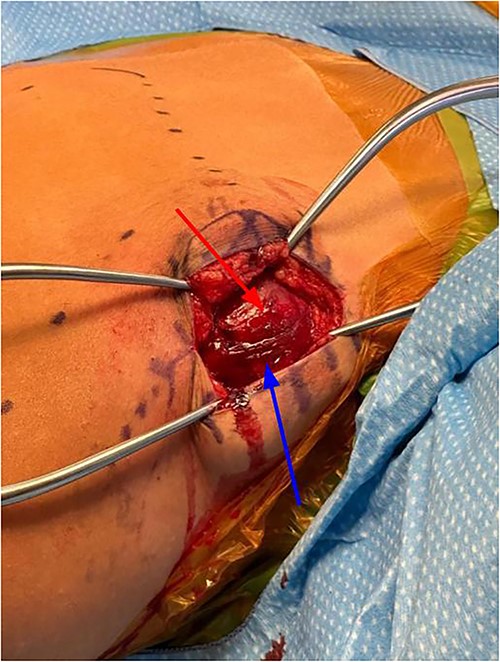

Subcutaneous tissue was divided with the electrocautery. Investing fascia over the trapezius was identified and the division between the superior and middle fibers of the trap was identified. The raphe between the superior and middle fibers was then bluntly spread in line (Fig. 3). We then encountered the superior aspect of the ventral lesion on the scapula (Fig. 4). Of note, the majority of levator scapulae fibers were medial to this lesion; however, the most lateral portion of the muscle was overlying the lesion. These lateral fibers were spread in line to expose the pedunculated mass. Blunt dissection was then taken circumferentially around the stalk of the mass to ensure all soft tissue had been freed from the area (Fig. 5). An osteotome was then carefully placed within the wound at the base of the stalk, and the tumor was then removed and sent to pathology for analysis. The stalk remnant was then filed down to a smooth and stable base with a rasp without any significant areas of potential irritation or prominence. The wound was then copiously irrigated with normal saline. Fluoroscopy images demonstrated complete resection of the bony tumor. There was no active bleeding within the wound. The fascia overlying the trapezius muscle and the skin were then closed.

Exposure after trapezius had been split between middle and superior fibers, levator scapula fibers can be seen medial to lesion (identified by arrow).

Exposure after scapula has been retracted and lesion was exposed, lesion can be directly visualized.